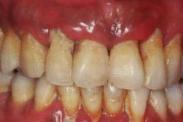

口腔粘膜病是指除腫瘤以外,發生在口腔粘膜和軟組織的疾病。口腔粘膜病病種較多,患病率較低,病損多種多樣,病因復雜,有些病與全身因素關系密切,在診治過程中要有整體觀念。口腔某一部位粘膜的正常色澤、外形、完整性與功能等發生改變的疾病。病變種類繁多,可以組合成復雜多樣的損害。有些全身性疾病也在口腔粘膜上有所表現,而有些口腔表征可作為全身疾病診斷的依據或線索。

- 常見癥狀:口舌潰爛、舌體干裂、聲音嘶啞 、口干口苦、口腔扁平苔癬、口腔炎、導致飲食困難、口腔疼痛難忍、反復發作